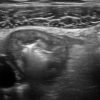

Viêm ruột

» Thông tin: Nữ giới – 18 tuổi.

» Lâm sàng: Tiêu chảy.